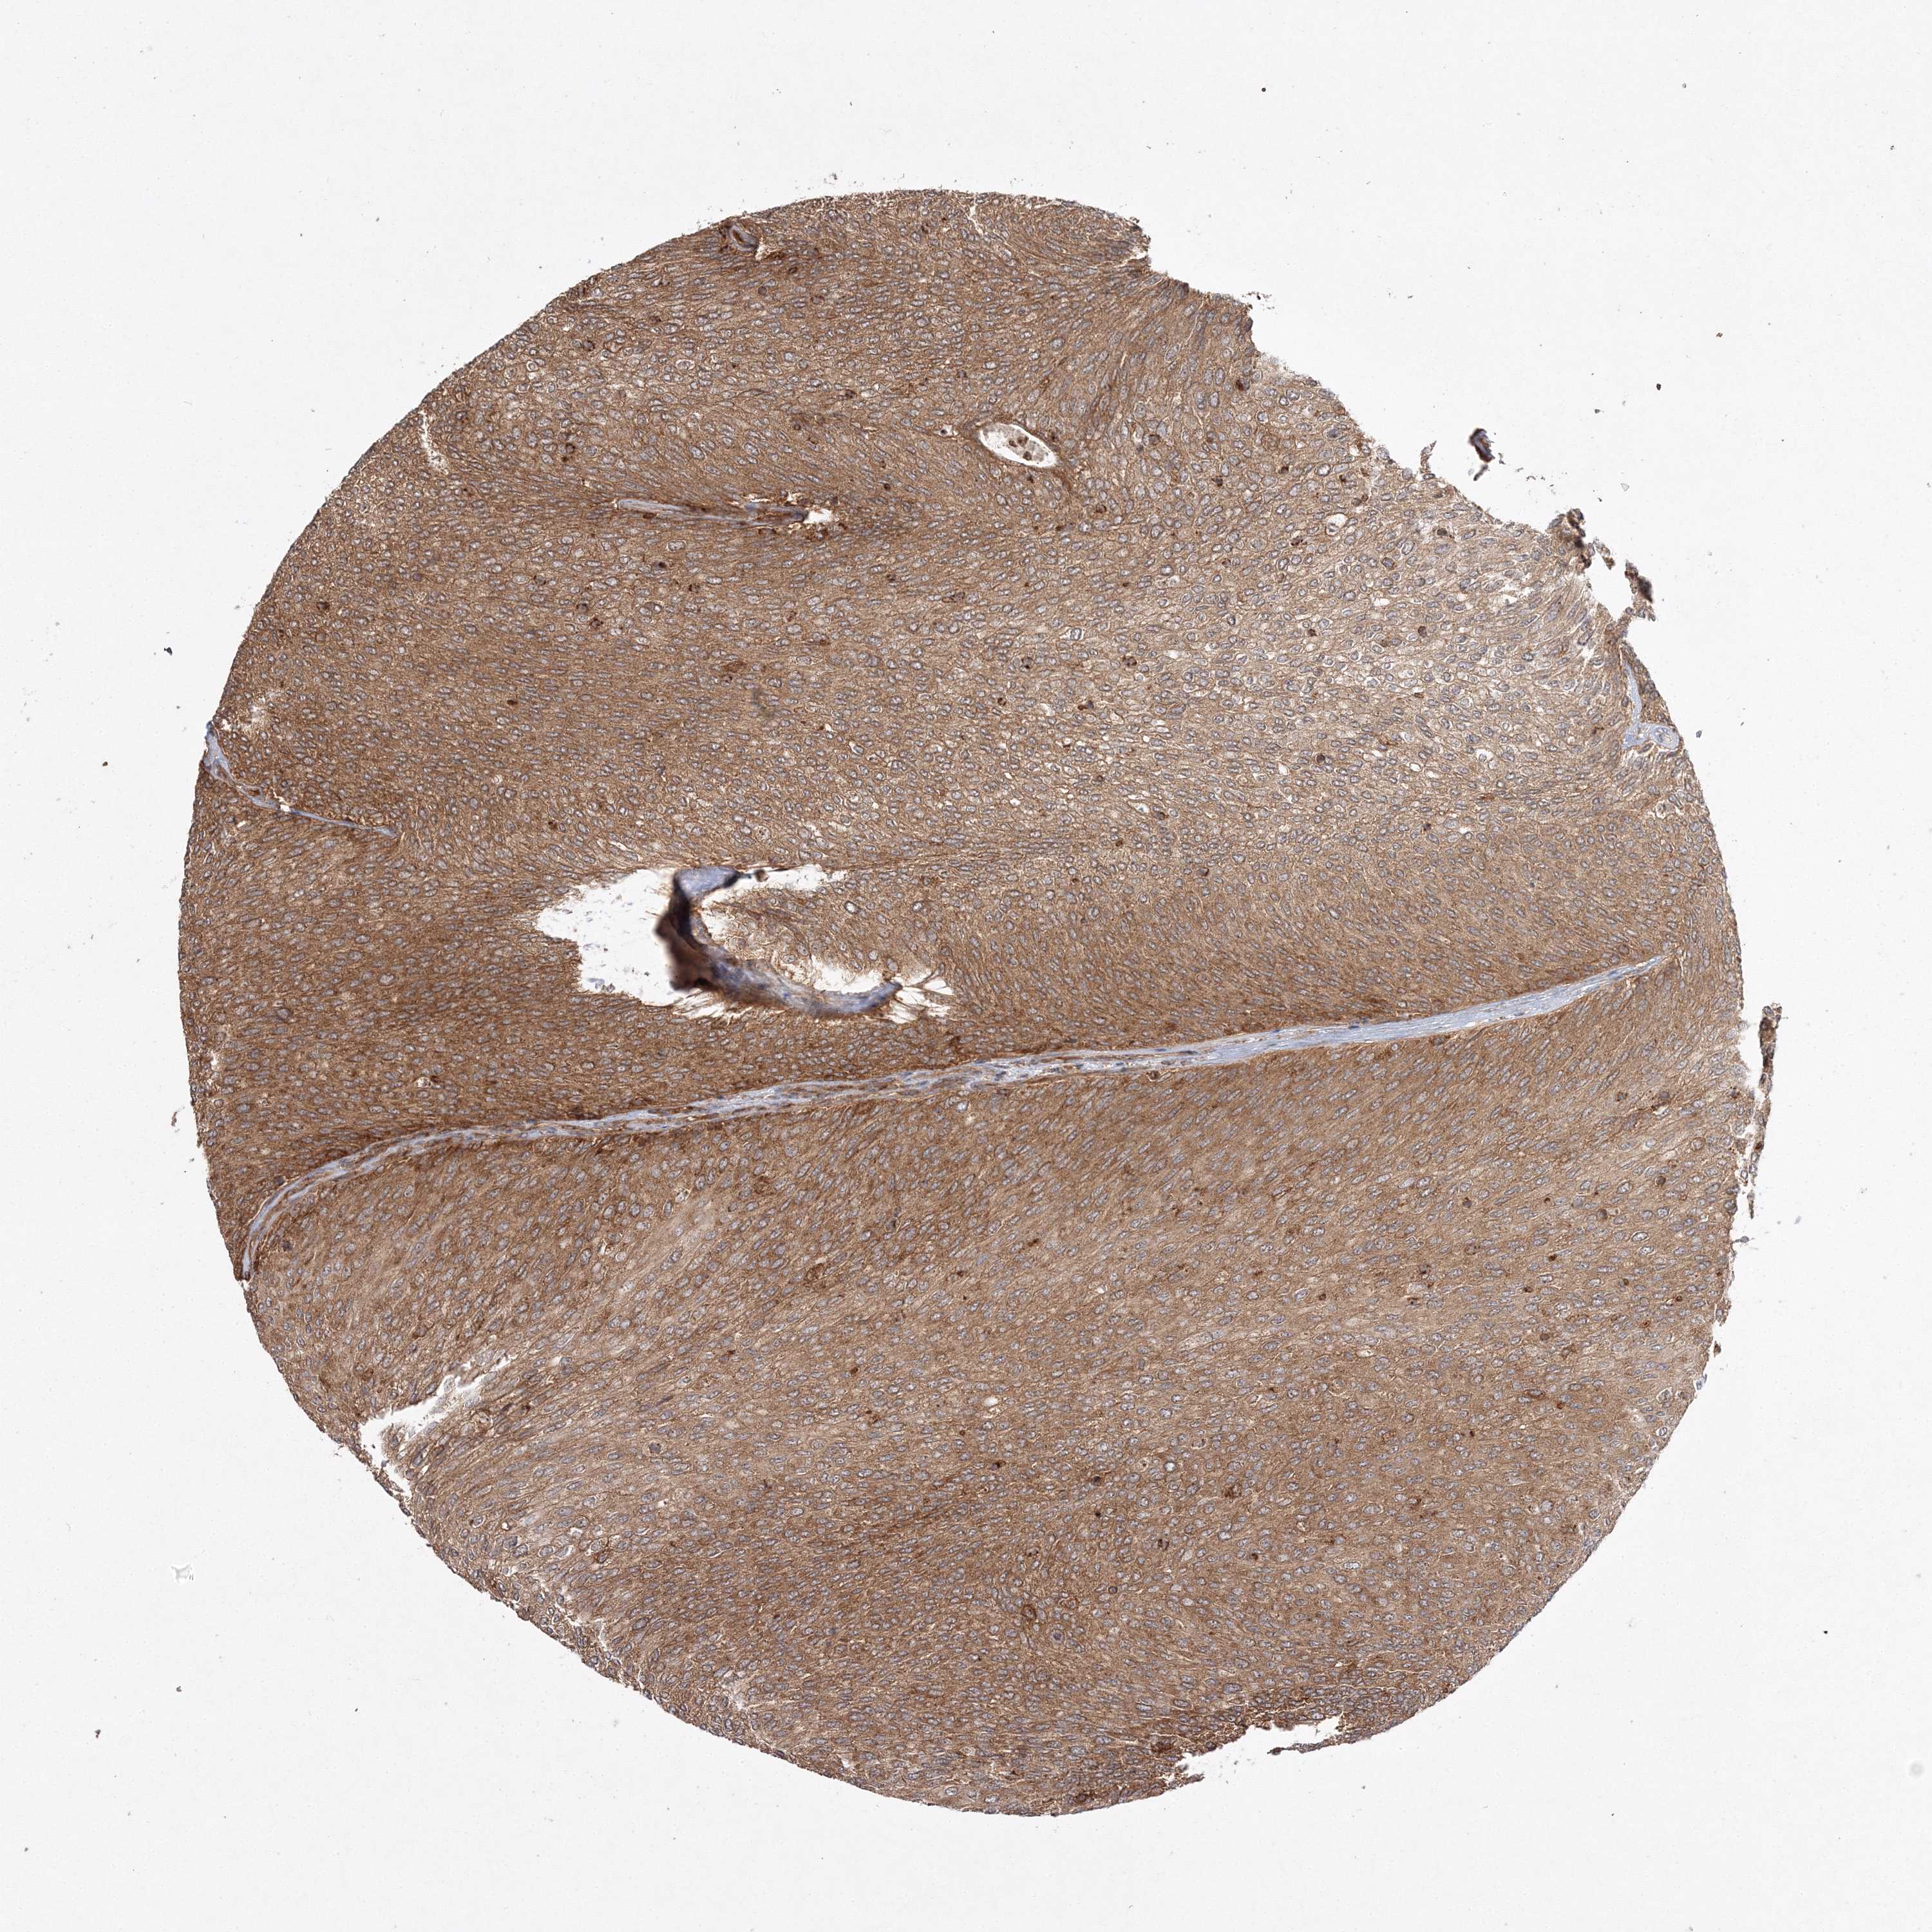

UROTHELIAL CANCER - Protein expressioni

A mouse-over function shows sample information and annotation data. Click on an image to view it in a full screen mode. Samples can be filtered based on level of antibody staining by selecting one or several of the following categories: high, medium, low and not detected. The assay and annotation is described here.

Note that samples used for immunohistochemistry by the Human Protein Atlas do not correspond to samples in the TCGA dataset.

Antibody stainingi

Antibody staining in the annotated cell types in the current human tissue is reported as not detected, low, medium, or high, based on conventional immunohistochemistry profiling in selected tissues. This score is based on the combination of the staining intensity and fraction of stained cells.

Each image is clickable and will lead to virtual microscopy that enables deeper exploration of all samples and also displays staining intensity scores, fraction scores and subcellular localization as well as patient and tissue information for each sample.

Antibody HPA037376

Antibody HPA037565

Staining

High

Medium

Low

Not detected

Intensity

Strong

Moderate

Weak

Negative

Quantity

>75%

75%-25%

<25%

None

Location

Nuclear

Cytoplasmic/membranous

Cytoplasmic/membranous,nuclear

Urothelial carcinoma, Low grade

Urothelial carcinoma, High grade